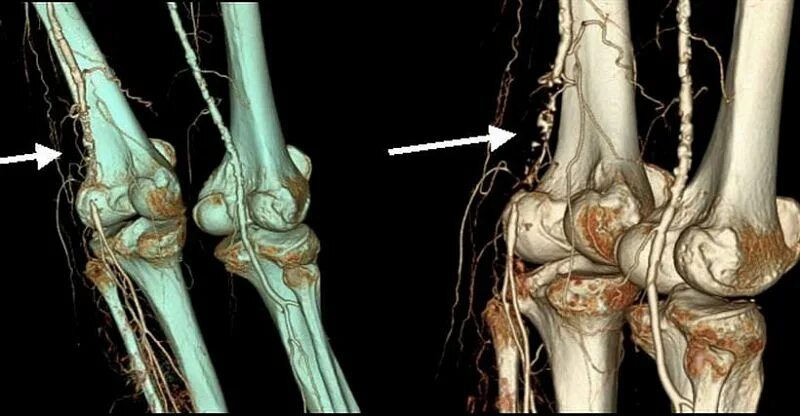

Кт суставов что показывает